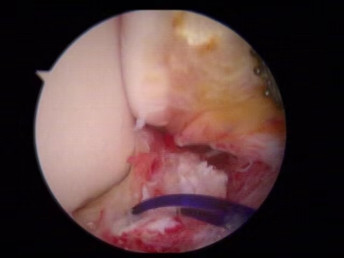

醫(yī)生們在手術中發(fā)現(xiàn),李先生的右踝關節(jié)軟骨損傷明顯,踝關節(jié)前方及內(nèi)外側均有不同程度的骨質(zhì)增生,相互撞擊引起疼痛,同時距腓前及跟腓韌帶斷裂。手術醫(yī)生利用磨鉆,小心翼翼將引起撞擊的骨刺一一去除,然后,修復了損傷的關節(jié)軟骨,最后,為他完成了距腓前和跟腓韌帶的修復。

修復斷裂的韌帶

術后第2天,李先生就可以穿戴步行靴下地并部分負重行走,踝部疼痛明顯減輕。,李先生現(xiàn)在基本恢復了運動功能,困擾他近10年的心理陰霾,也終于一掃而清。